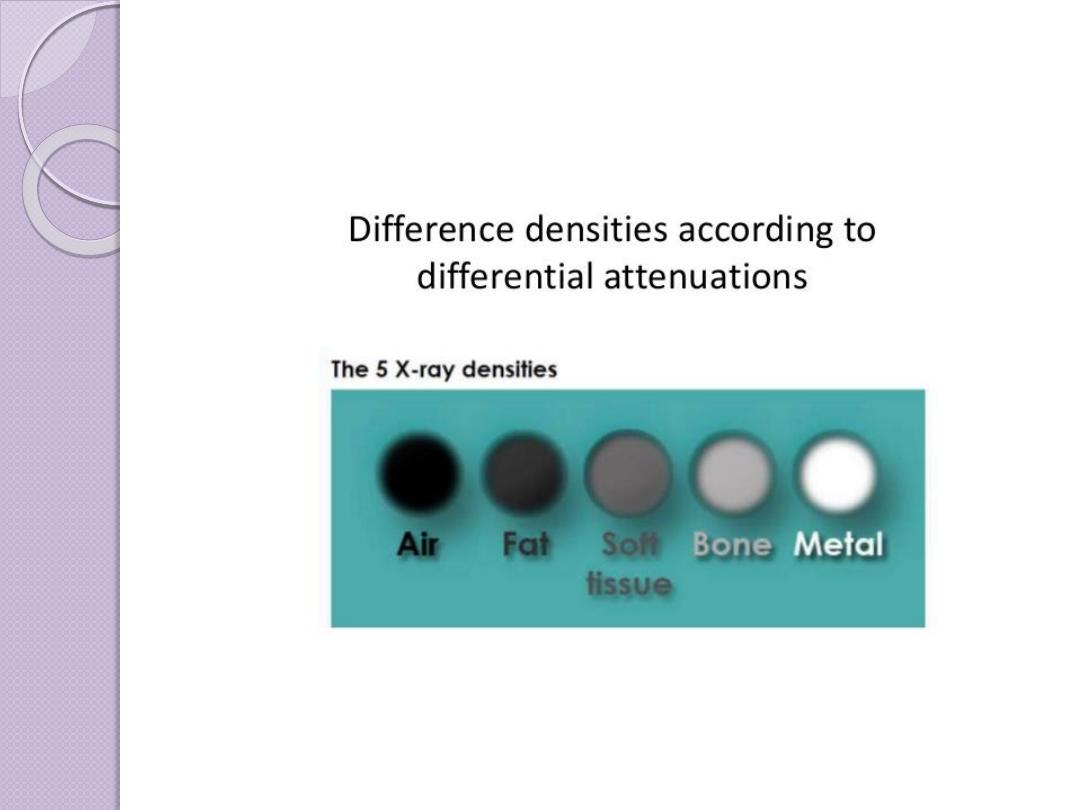

Basic radiographic densities

Principles of Interpretation

Conventional radiographs demonstrate

five basic

radiographic densities: air, fat, soft tissue,water, bone, and

metal

(or x-ray contrast agents). Air attenuates very

little of the x-ray beam, allowing nearly the full force of

the beam to blacken the image. Bone, metal, and

radiographic contrast agents attenuate a large

proportion of the x-ray beam, allowing very little

radiation through to blacken the image. Thus, bone,

metallic objects, and structures opacified by x-ray

contrast agents appear white on radiographs. Fat and

soft tissues attenuate intermediate amounts of the x-ray

beam, resulting in proportional degrees of image

blackening (shades of gray)

.